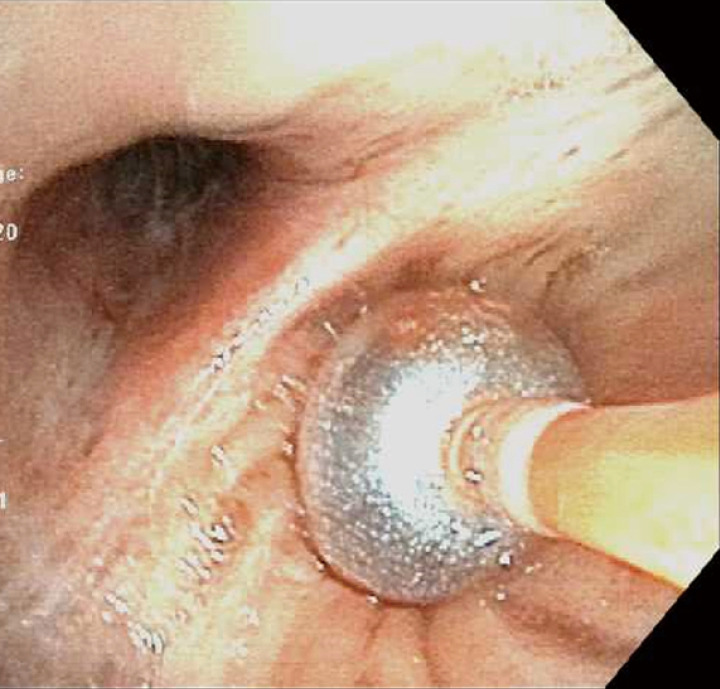

Figure 2.

An 80-year-old gentleman presented with acute respiratory failure requiring intubation and mechanical ventilation, a few hours after a witnessed choking episode with the first bite of a “hot-dog”. Cryotherapy extraction of the foreign body was performed and the patient was extubated the following morning. He received a short course of antibiotics to manage post-obstructive pneumonia.